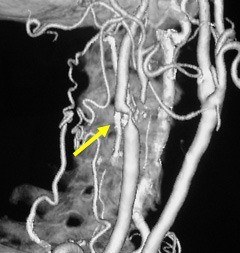

写真左:術前頚動脈狭窄所見

写真右:術後所見 外科手術によって頚動脈狭窄は改善している